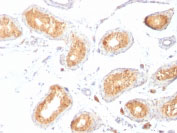

Formalin-fixed, paraffin-embedded human Testis stained with gp100 / Melanosome Monoclonal Antibody (HMB45). |